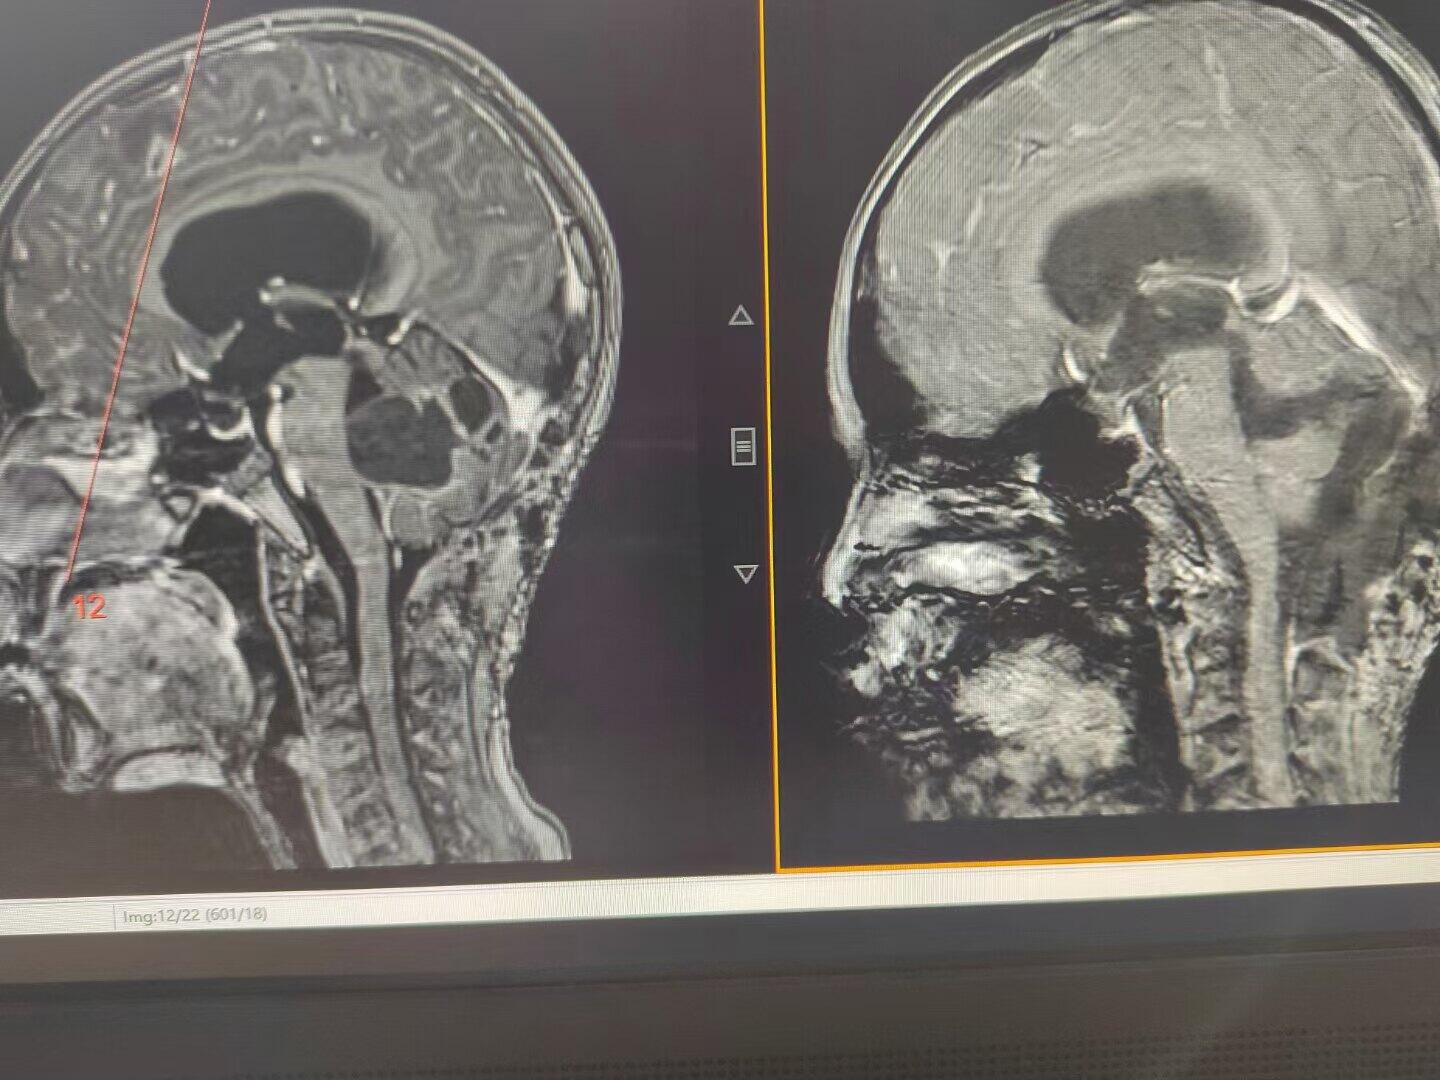

后颅窝占位引起梗阻性脑积水,术前已经出现视力模糊,脑室ommaya测压大于50cm水柱,临时外引流缓解颅压后患儿视力有恢复,后急诊行后颅窝占位切除,术中切除囊性占位、打通中脑导水管、解除脑干压迫,术后脑积水缓解满意,患儿状态良好。